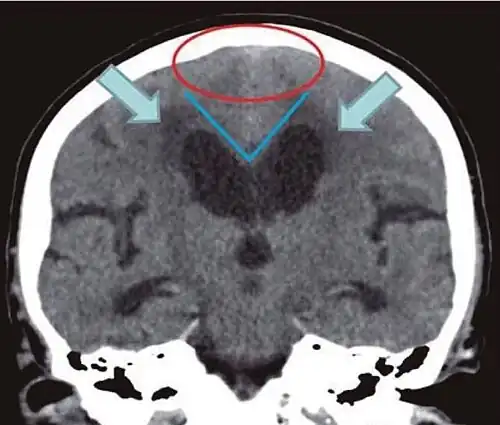

• Imaging from magnetic resonance imaging (MRI) or computed tomography (CT) is needed to demonstrate enlarged ventricles and no macroscopic obstruction to cerebrospinal fluid flow. Imaging should show an enlargement to at least one of the temporal horns of lateral ventricles, and impingement against the falx cerebri resulting in a callosal angle ≤ 90° on the coronal view, showing evidence of altered brain water content, or normal active flow (which is referred to as "flow void") at the cerebral aqueduct and fourth ventricle.

Typical imaging findings in normal pressure hydrocephalus versus brain atrophy.[21]

Normal pressure hydrocephalus Brain atrophy

Preferable projection Coronal plane at the level of the posterior commissure of the brain.

Modality in this example CT MRI

CSF spaces over the convexity near the vertex (red ellipse ) Narrowed convexity ("tight convexity") as well as medial cisterns Widened vertex (red arrow) and medial cisterns (green arrow)

Callosal angle (blue V) Acute angle Obtuse angle

Most likely cause of leucoaraiosis (periventricular signal alterations, blue arrows ) Transependymal cerebrospinal fluid diapedesis Vascular encephalopathy, in this case suggested by unilateral occurrence